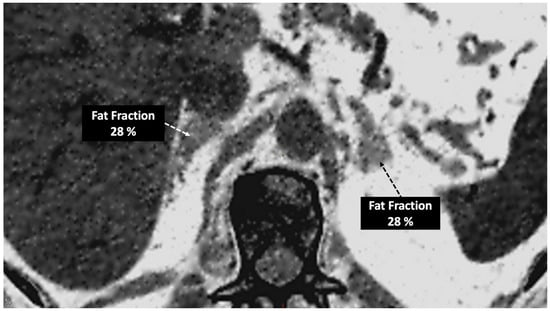

- In the case of adrenal imaging, the fat fraction has higher sensitivity than VUE attenuation and the traditional threshold of 10 HU or lower for diagnosing adrenal adenomas. Loonis et al. [20] reported a fat fraction threshold of ≥23.8% with 100% specificity and 59% sensitivity (Figure 11). Furthermore, DECT-derived parameters can be used to differentiate adrenal adenoma from pheochromocytoma, or metastases based on the effect of lipid components on attenuation [33,34]. Finally, the iodine concentration can also be an imaging marker of dominant adrenal lesions in functional syndromes [35].

Figure 11. Adrenal adenoma. Fat fraction of adrenal lesions evaluated with DECT may be an alternative diagnostic tool to VUE attenuation using the traditional threshold of 10 HU or lower in the assessment of adrenal adenomas. Fat quantification DECT image evidences bilateral lipid-rich adrenal adenomas with increased fat fraction. - Breast imaging. DECT seems to be a reliable tool for diagnosis and locoregional staging of breast cancer [36,37,38,39,40] (Figure 12). Klein et al. [37] found robust cut-off points for the differentiation of benign and malignant lesions (Zeff < 7.7, iodine content of <0.8 mg/mL). The DECT quantitative parameters may also be useful in predicting breast cancer invasiveness and histopathological and molecular subtypes of breast tumors. In the case of node staging, the similarity of quantitative DECT parameters between the primary lesion and axillary LNs may predict axillary metastasis in breast cancer [40,41].